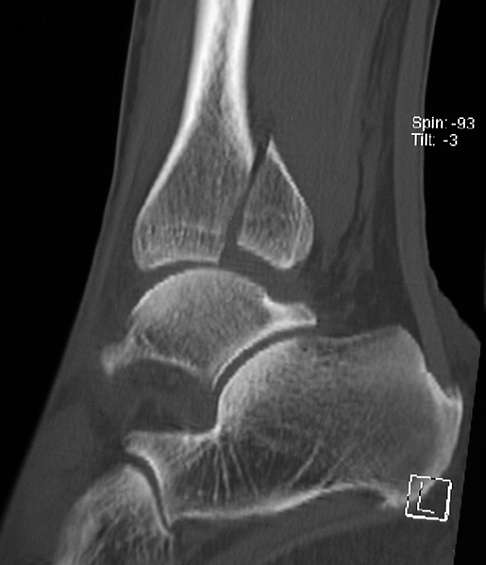

Diagnose: Wie untersucht der Orthopäde das Sprunggelenk?

Nach einer Sprunggelenksfraktur spüren alle Patienten sofort einseitig heftige Schmerzen und eine resultierende Instabilität beim Gehen und Stehen. Gehen ist nach einem Knöchelbruch nicht mehr möglich. Die Schwellung des Knöchels als Frakturfolge ist ein deutliches Signal für den untersuchenden Orthopäden. Der Hergang des Unfalls ist aufschlussreich, um die Art der zu erwartenden Schäden genauer abzuschätzen. Wie bei jeder Knochenfraktur stellt der Orthopäde die Diagnose vor allem mithilfe der Röntgenuntersuchung.

Die Heilung der Fraktur wird durch Röntgenbilder überwacht. Dabei überprüft der Orthopäde in erster Linie die Stellung des Sprunggelenks. Erst bei nachgewiesener Heilung darf der Gips entfernt werden. Nach der Gipsabnahme ist zusätzlich eine Nachbehandlung notwendig, um Muskulatur und Koordination des betroffenen Beines wiederherzustellen. Das bedeutet, dass schon so viel Bewegung wie möglich erlaubt wird, aber noch so viel Ruhigstellung erfolgt, wie erforderlich ist.